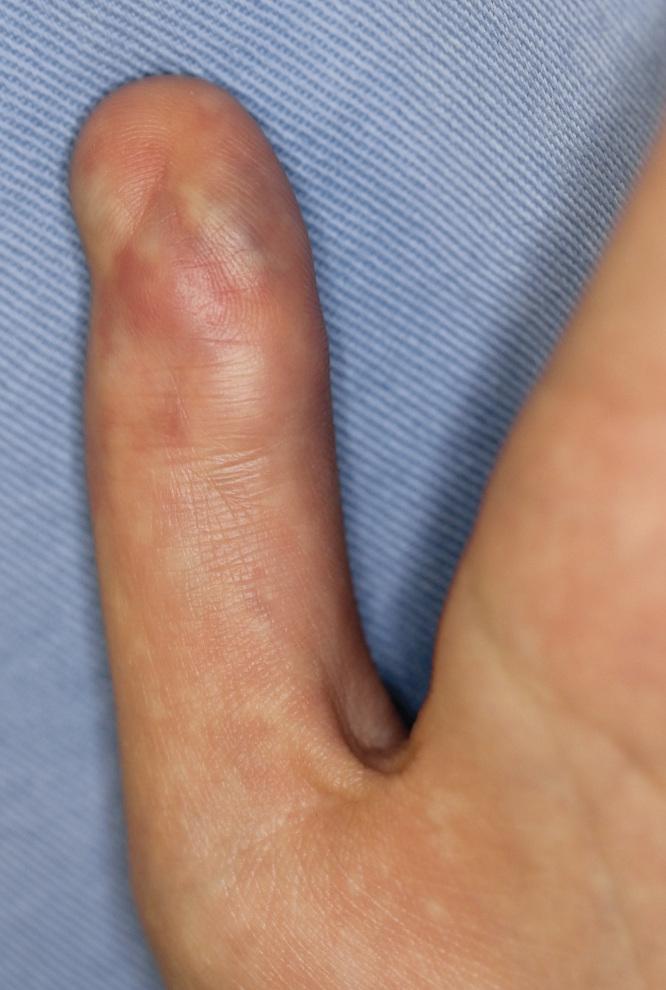

Vascular malformations of bone are complex lesions that can cause deformity and pain. A combined soft tissue and intraosseous venous malformation of the left thumb in a girl was treated with two sessions of ethanol sclerotherapy using a bone marrow aspiration needle under fluoroscopic guidance.

骨血管畸形是一种复杂的病变,可导致畸形和疼痛。一名女孩左拇指的软组织和骨内静脉联合畸形,在透视引导下使用骨髓穿刺针进行了两期乙醇硬化治疗。